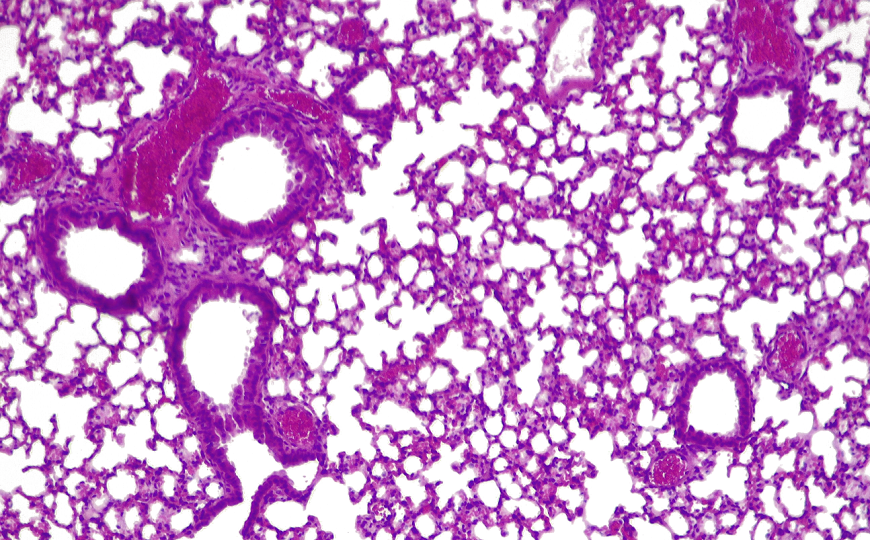

Затем ученые проверили модифицированный штамм M. pneumoniae на мышиной модели острой легочной инфекции, вызванной синегнойной палочкой. Введение модифицированных микоплазм в органы дыхания грызунов привело к заметному улучшению состояния их легких. Микоплазмы удвоили выживаемость мышей по сравнению с контрольной группой без лечения. Гистопатология легких показала выраженное снижение поражения легких, также в легких мышей были снижены концентрации маркеров воспаления. Инженерная бактерия активно уничтожала синегнойные палочки при помощи пиоцинов и ферментов, растворяющих биопленки. Введение однократной высокой дозы препарата не выявило признаков токсичности в легких. После завершения терапии иммунная система животных полностью избавилась от модифицированных бактерий в течение четырех дней.